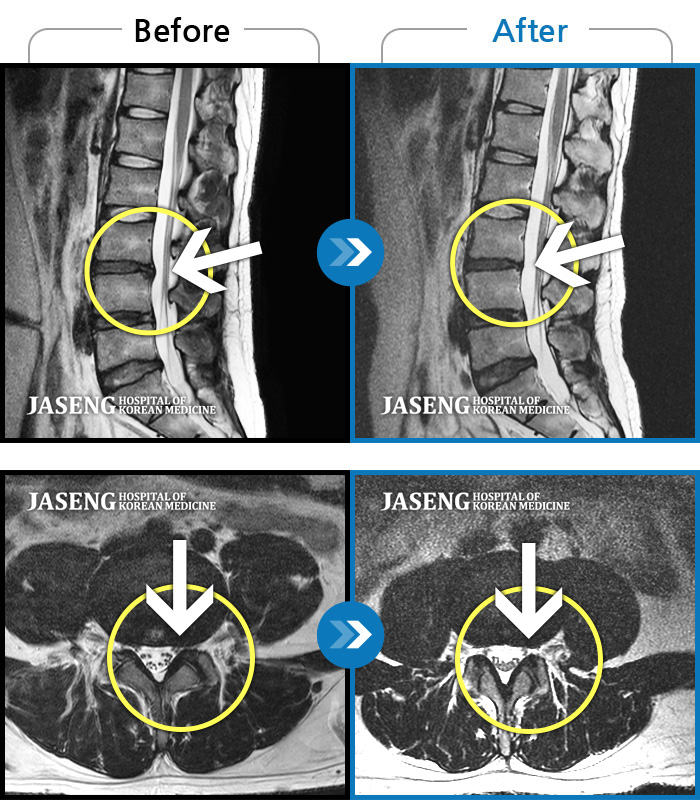

Before

After

환자에게 사전 동의를 받아 동일 조건에서 촬영되었습니다.

개인에 따라 치료 후 부작용이 발생할 수 있으니 의료진과 상담 후 치료를 진행하시기 바랍니다.

허리통증 및 골반부위 통증으로 일상생활이 불가능했습니다.

하요추부 통증과 하지 저림